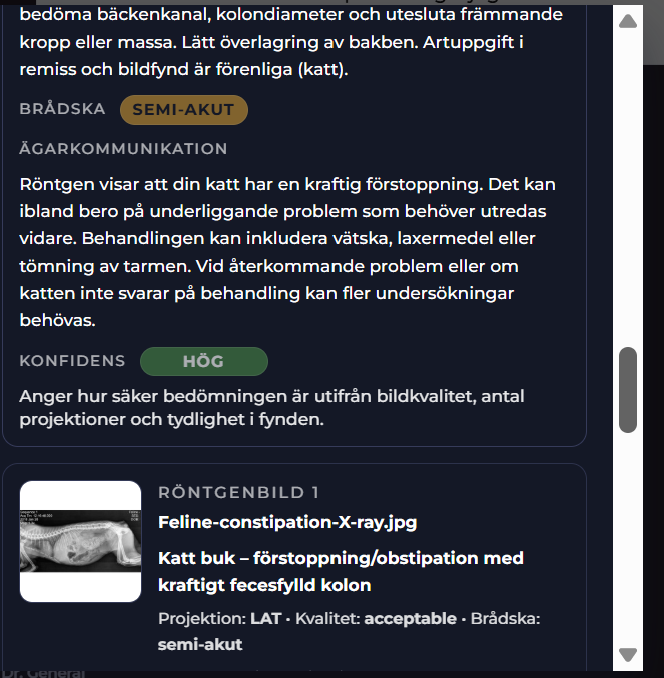

Radiologica Röntgentolk har utgått från chatt med din doktor som har en frågeställning som ska utredas. I detta exempel är det en katt som kan vara förstoppad. En komplett remiss har producerats. Remissens frågeställning tillsammans med röntgenbilder du kan ladda upp kommer att tolkas och generera ett remissvar.

I Stetoskåpet med Visuella Fynd (Röntgen) finner du ett strukturerat remiss-svar och rekommendationer. Din AI-doktor hanterar dessa resultat och återupptar chatten med dig. Du kan när som helst klicka på olika submenyer i Steoskåpet för hela statusen i ärendet.

Radiologica - Komplett remisssvar

I Visuella fynd (Stetoskåpet) finner du det kompletta remisssvaret. I remisssvaret kan du du titta på den strukturerade labrapporten samt läsa Labora´s svar på frågeställningen. Labora kommer svara både övergripande och i detalj för de enskilda biomarkörerna smat ge en rekommendation till din chatt AI doktor.

I detta simulerade fall finns förslag på remiss, diagnos, rekomendation, akutläge etc i stetoskåpet.

Vi även lagt till att det faktiskt tas röntgenbilder baserat på remissen och AI-doktorns rekomendation baserat på denna. Detta sker självklart inte samtidigt i praktiken då djurägaren först måste komma in till kliniken och göra dessa föreslagna röntgenbilder.